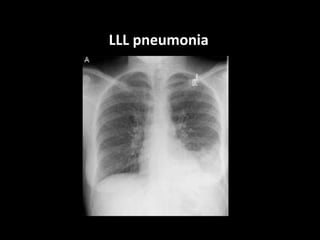

LLL pneumonia